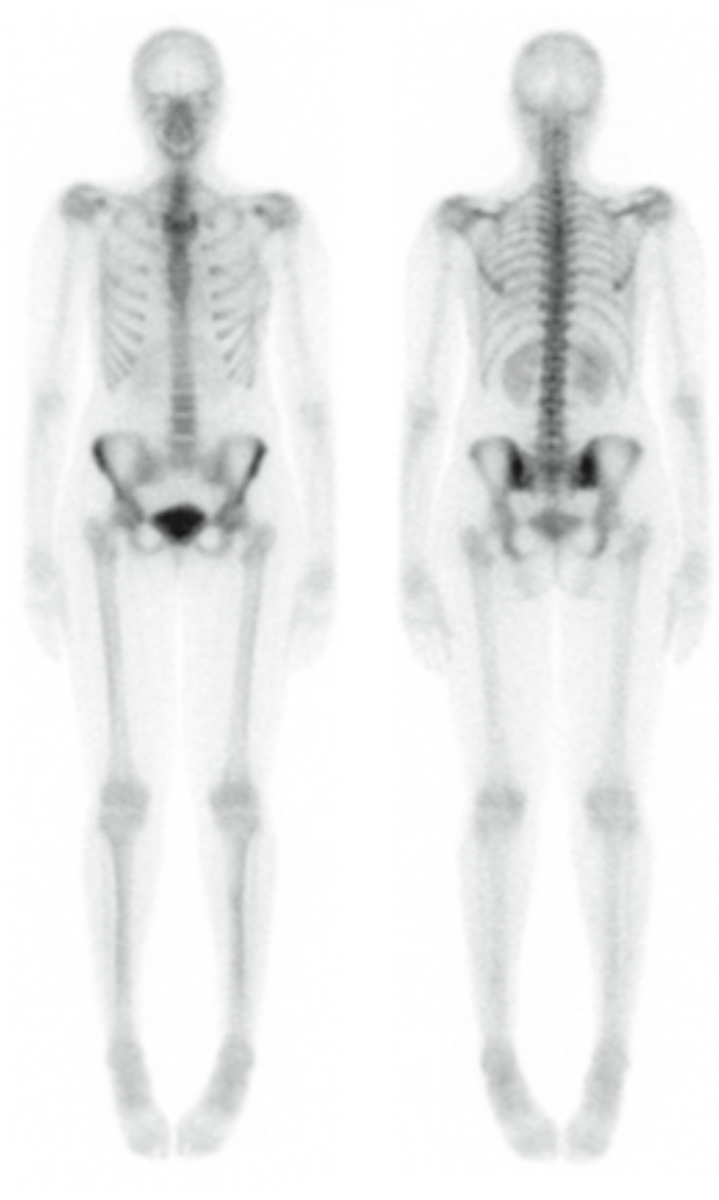

• Cintilografia Óssea

• Pesquisa de Corpo Inteiro (P C I)